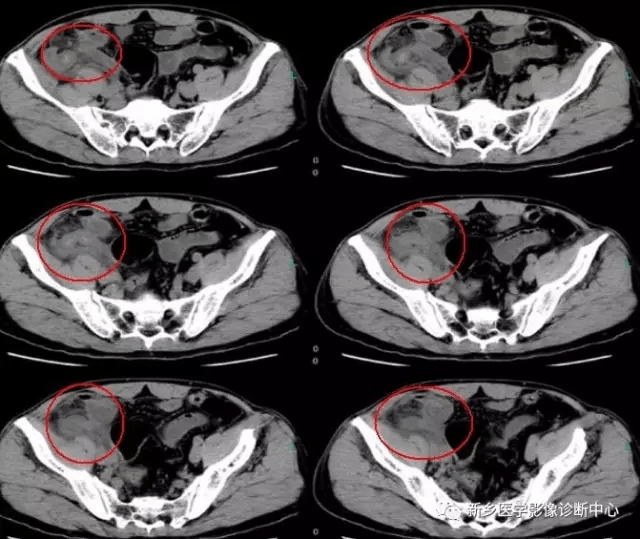

11 腹股沟疝

文章图片